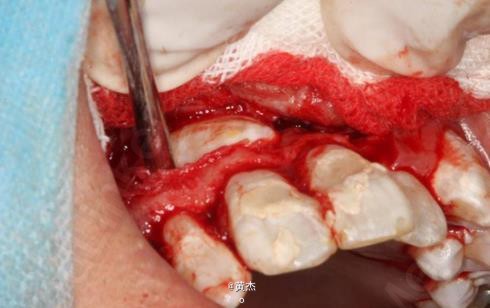

诊断:11、21根尖周炎。处理:11、21开髓无活力,大量血性渗出,根管无法测量。于是转诊口腔外科。术前和患者签知情同意书。给患者讲明外科手术有可能失败,最终拔除11、12、21的可能性。口腔外科处理:拔除13.。发现 11牙根几乎完全吸收、21唇侧牙根也被13牙冠压迫吸收到根中1/3。于是术中行11、21MTA根尖区封闭。12暂不做处理,观察半年后考虑进一步治疗方案。